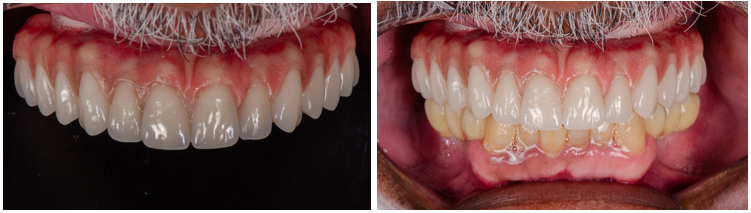

Em consonância com o que foi ressaltado, é válido ressaltar que o objetivo principal é, através da reabilitação oral, restabelecer a função, a estética e a saúde bucal de pacientes com perdas dentárias ou edentulismo total. Essa abordagem envolve a restauração de aspectos funcionais, como a eficiência mastigatória e o conforto e estabilidade oclusal, além de garantir a harmonia estética do sorriso.

Dessa forma, este relato de caso visa explorar a aplicação prática da reabilitação oral total, em maxila e em mandíbula. Foi realizada a combinação entre prótese protocolo superior e a instalação de implantes e prótese implantossuportada de zircônia no arco inferior.

Por fim, o tratamento finalizou com a carga precoce dos implantes que culminam na instalação dos pônticos de zircônia sobre os implantes.